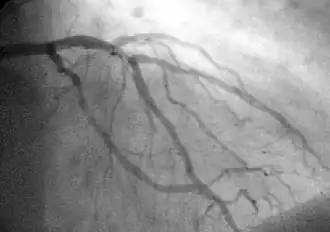

![]() A coronary angiogram showing the circulation in the left coronary artery and its branches. | |

The interventional cardiologist uses the entry point created during the percutaneous access step, to introduce the catheter system and guides it to the occluded area of the coronary artery being treated, using fluoroscopy and radiopaque dyes as an imaging tool. The device and its balloon/stent components can be inflated to open the stenotic diseased artery area. When a stent is used, the stent tube mesh is initially collapsed onto the balloon component of the catheter. In this collapsed state, it is small enough to be passed though relatively narrow peripheral arteries and then inflated by the underlying balloon and pressed firmly against the diseased coronary artery wall. It is expanded by pressure introduced by injecting physiological saline into the device through the lumen of the still attached catheter. Inflation time and pressure used are recorded during this placement procedure. After the balloon inflation/deflation or the deposition of the stent, the placement device/deflated balloon are removed leaving the stent in place.[21][22]

The interventional cardiologist decides how to treat the blockage in the best way during the PCI/stent placement, based on real-time data. The cardiologist uses imaging data provided by both intravascular ultrasound (IVUS), and fluoroscopic imaging (combined with a radiopaque dye) during the procedure. The information obtained from these two sources enables the cardiologist to track the path of the catheter-device as it moves through the arterial vessels. This information also helps determine both the location and physical characteristics of plaque(s) causing narrowing in the arteries. Data from these two techniques is used to correctly position the stent and to obtain detailed information relating to the coronary arterial anatomy. This anatomy varies greatly among individuals, having this information becomes crucial for effective treatment. The obtained data is recorded on video and is of value in cases when future treatment is needed.[23][24][25][26]